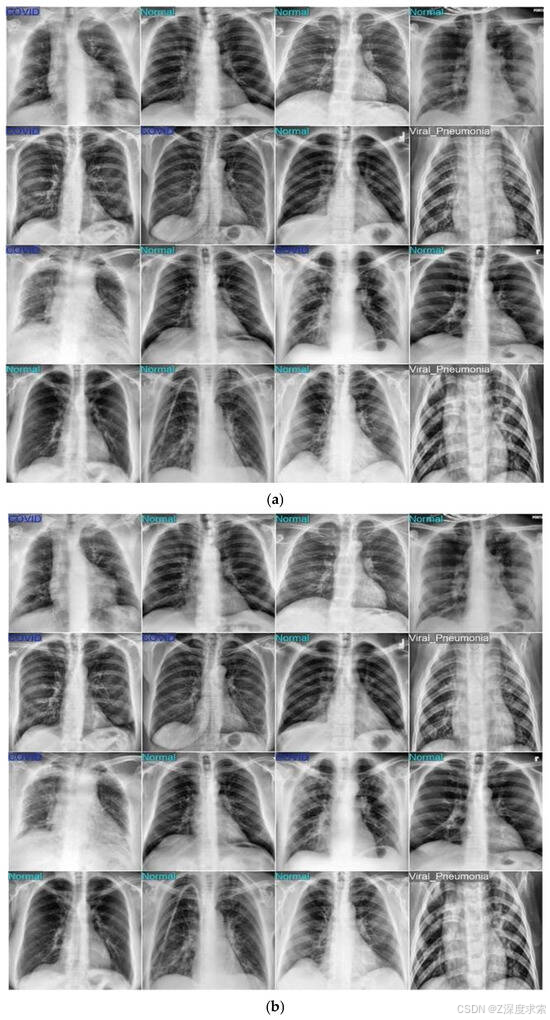

在 COVID-19 放射线照相数据库上进行训练和测试后,所提出的基于 YOLOv11 的肺炎检测模型在所有三个类别(COVID-19、正常和肺炎)中都取得了出色的性能。图 4 说明了模型的学习行为,训练和验证损失在连续的时期稳步下降,训练准确性持续提高,表明有效收敛,没有过度拟合的迹象。图5中的混淆矩阵证实了高分类准确性,只有少数错误分类,每个类别的敏感性和特异性都很强。图 6 中的可视化示例进一步验证了这些结果,显示了真实标签(图 a)和模型预测(图 b)之间的密切匹配。不同胸部 X 光样本的高度一致性凸显了该框架在准确区分 COVID-19、正常和肺炎病例方面的可靠性和稳健性。

图6.使用数据集 1、(a) True 标签和 (b) 预测标签的模型预测样本

使用第二个数据集(胸部 X 光、COVID-19 和肺炎),所提出的 YOLOv11 框架在所有三个类别中都取得了一致的强劲成果。图 8a-c 显示了训练行为,其中训练和验证损失均稳步下降,准确率在稳定之前迅速升至 98% 以上,表明有效收敛,没有过度拟合的证据。图 9 中的混淆矩阵仅突出显示了少量错误分类:20 次正常扫描预测为肺炎,5 例肺炎病例被归类为正常,以及一张肺炎图像被错误标记为 COVID-19。这表明了明显的类别分离,特别是对于 COVID-19,它达到了近乎完美的准确性。图 10 进一步说明了这种可靠性,因为预测的标签与地面实况注释非常匹配,差异最小。